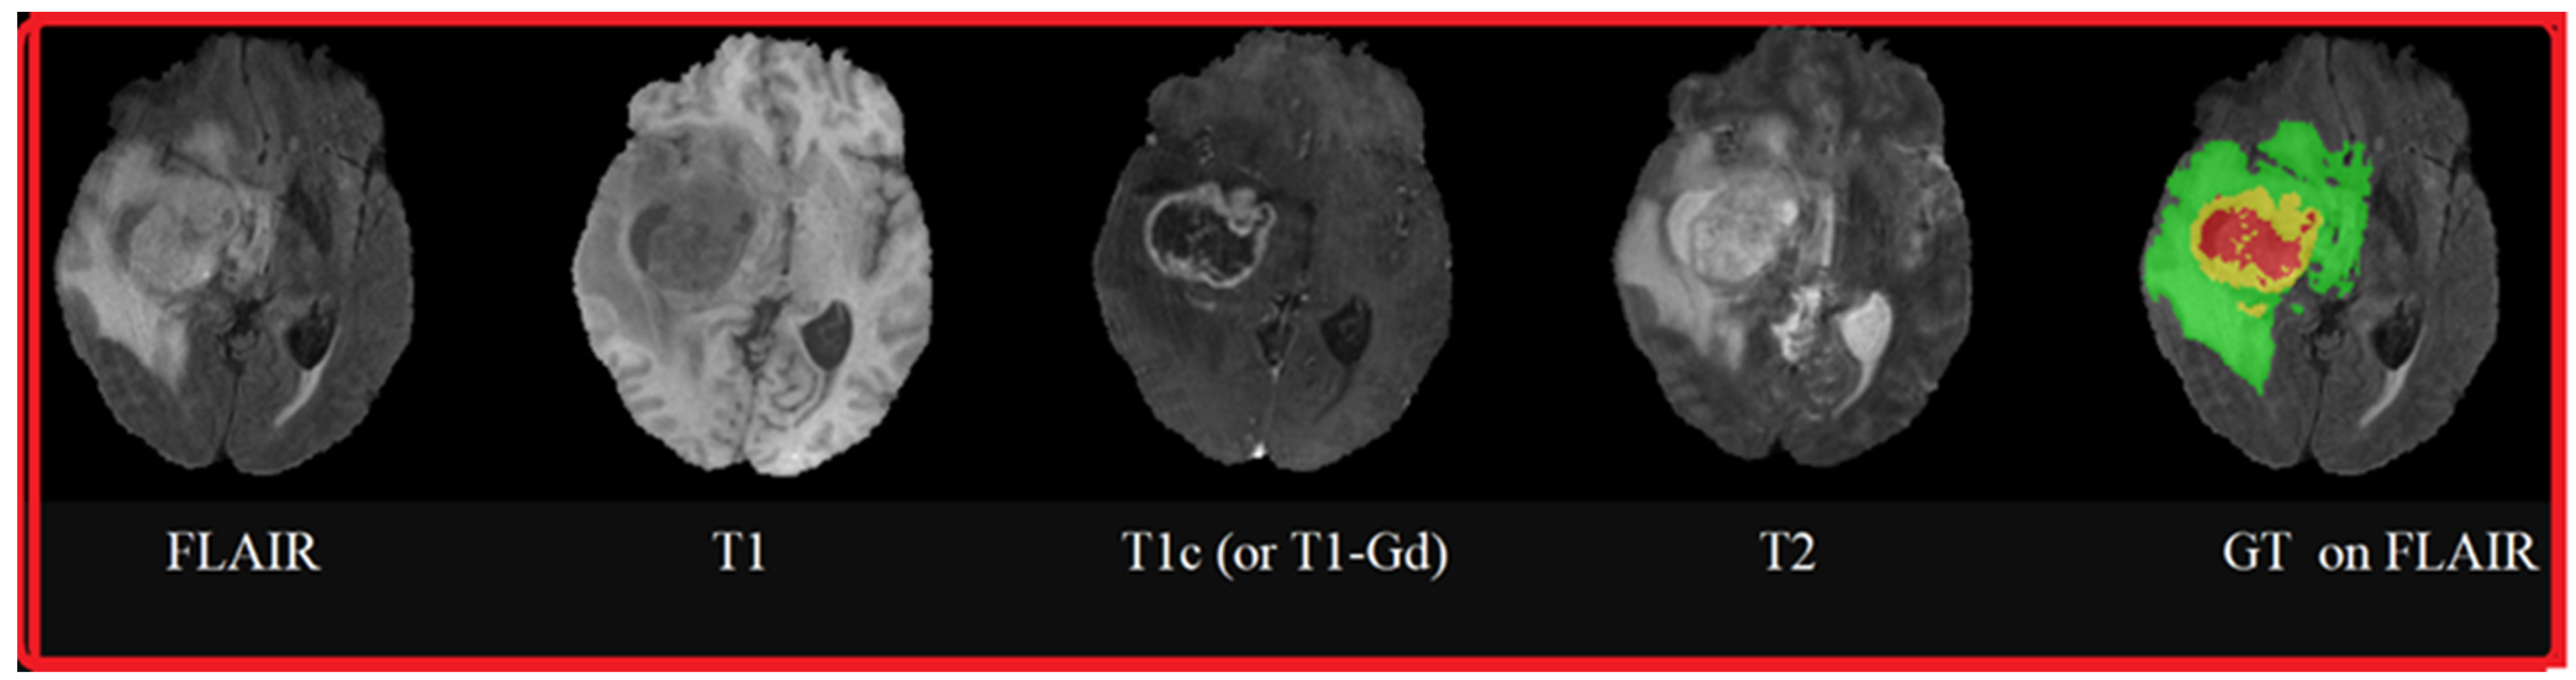

4.2. Experiments on the BraTS 2015 Database

4.2.1. Database Description

4.2.2. Experiments